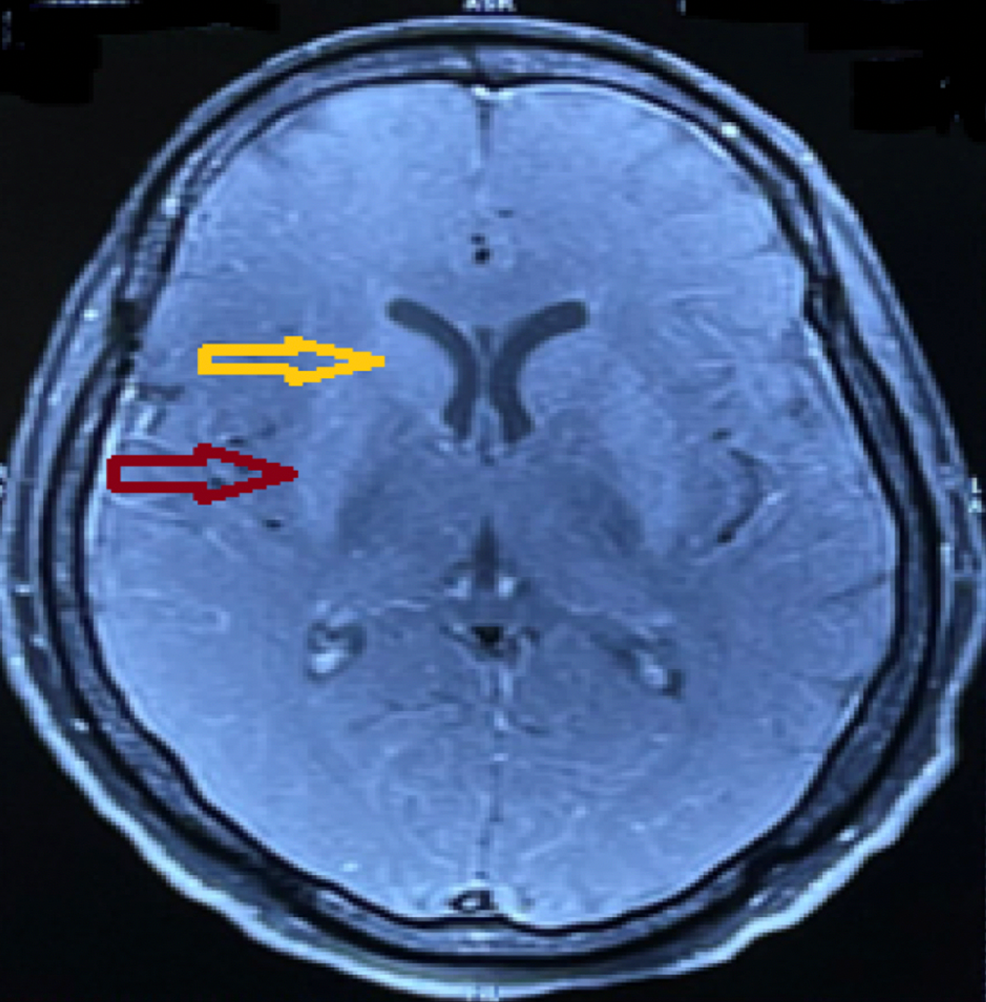

From www.researchgate.net

(A) T1weighted axial image showing hyperintensity on basal ganglia and Basal Ganglia Encephalitis Test Csf antibody assay appears to be more specific, consistent, and reliable than serum testing for autoimmune encephalitis arising. Mayo clinic is working to improve outcomes for individuals with autoimmune encephalitis, an often complex disease that can cause persistent cognitive and physical deficits. The inflammation interferes with basal ganglia functions, leading to a variety of behavioral, psychiatric, and neurologic symptoms. Involvement. Basal Ganglia Encephalitis Test.

A, B Brain MR imaging showing basal ganglia T2 hyperintense (A) and T1 Basal Ganglia Encephalitis Test The inflammation interferes with basal ganglia functions, leading to a variety of behavioral, psychiatric, and neurologic symptoms. Encephalitis is a severe inflammatory disorder of the brain with many possible causes and a complex differential diagnosis. Involvement of the thalamus or basal ganglia (t/bg) occurs in a subset of patients with encephalitis and may be an important. Csf antibody assay appears. Basal Ganglia Encephalitis Test.